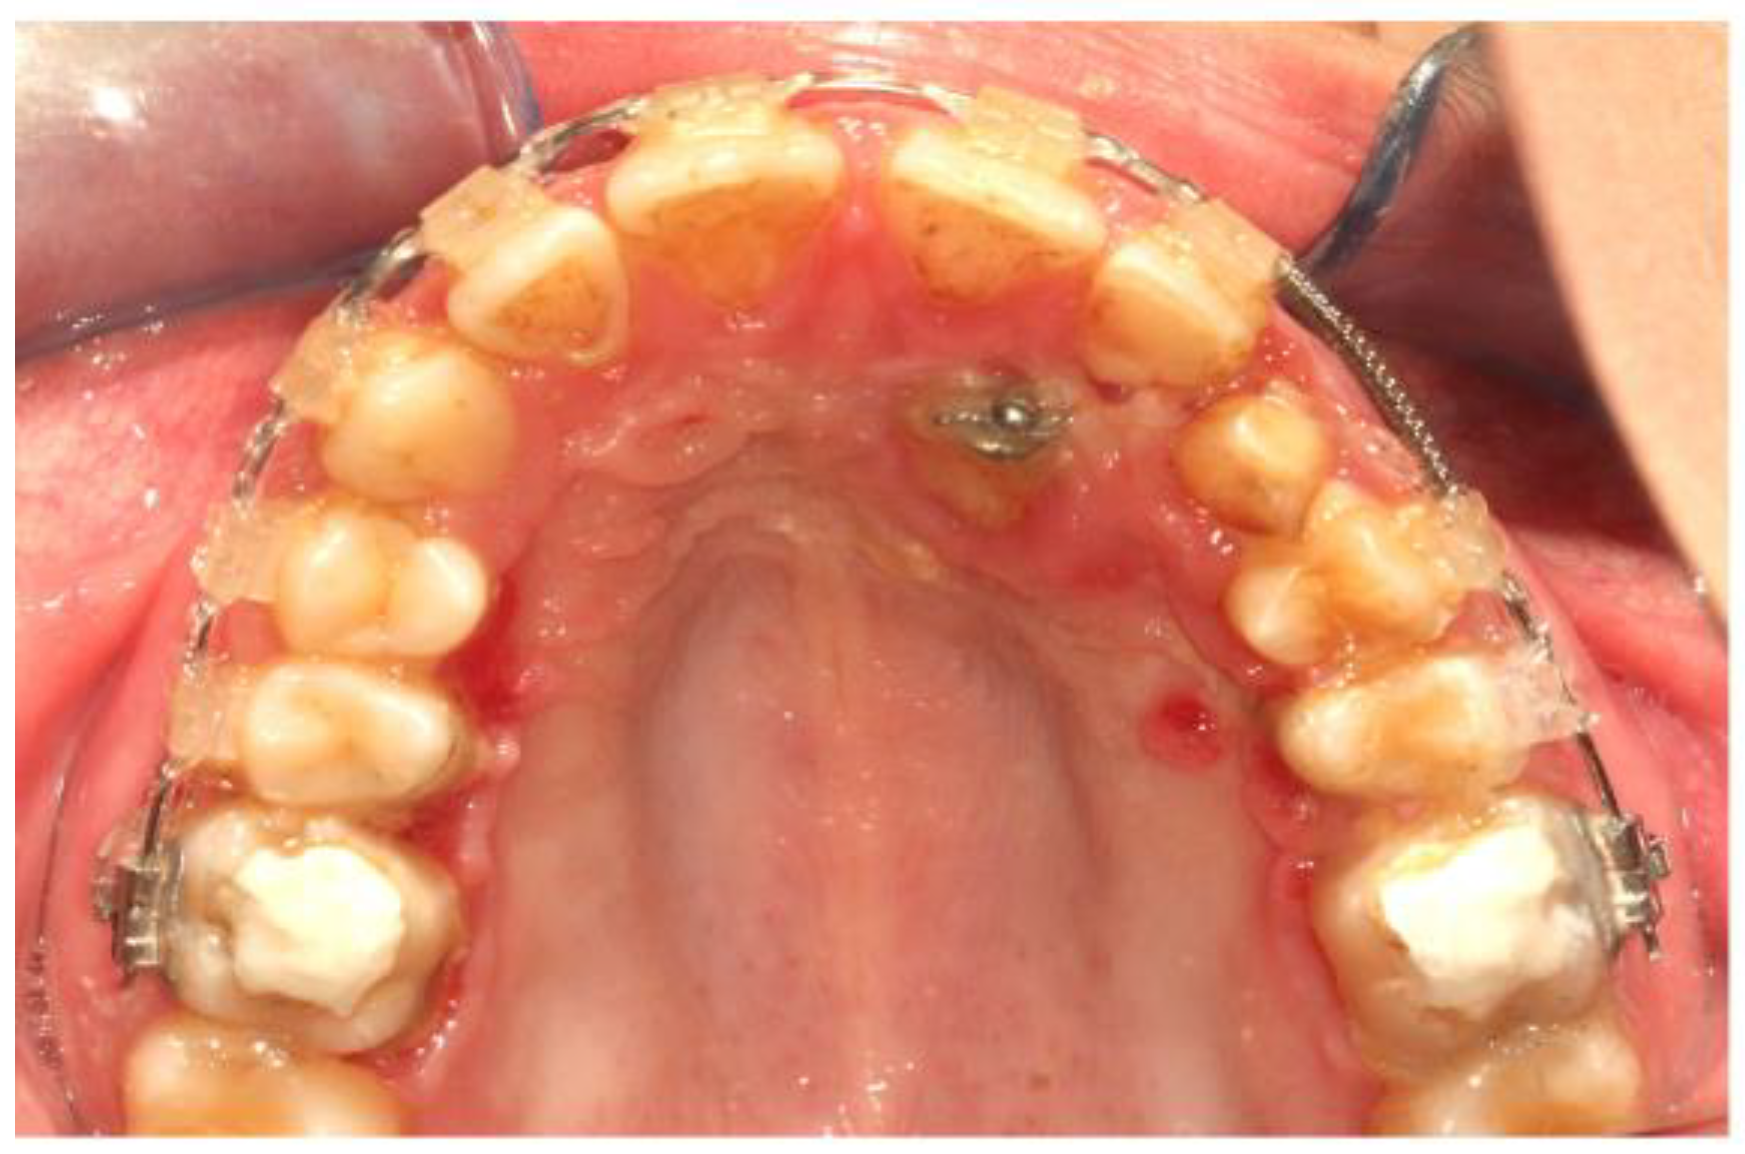

3. Results